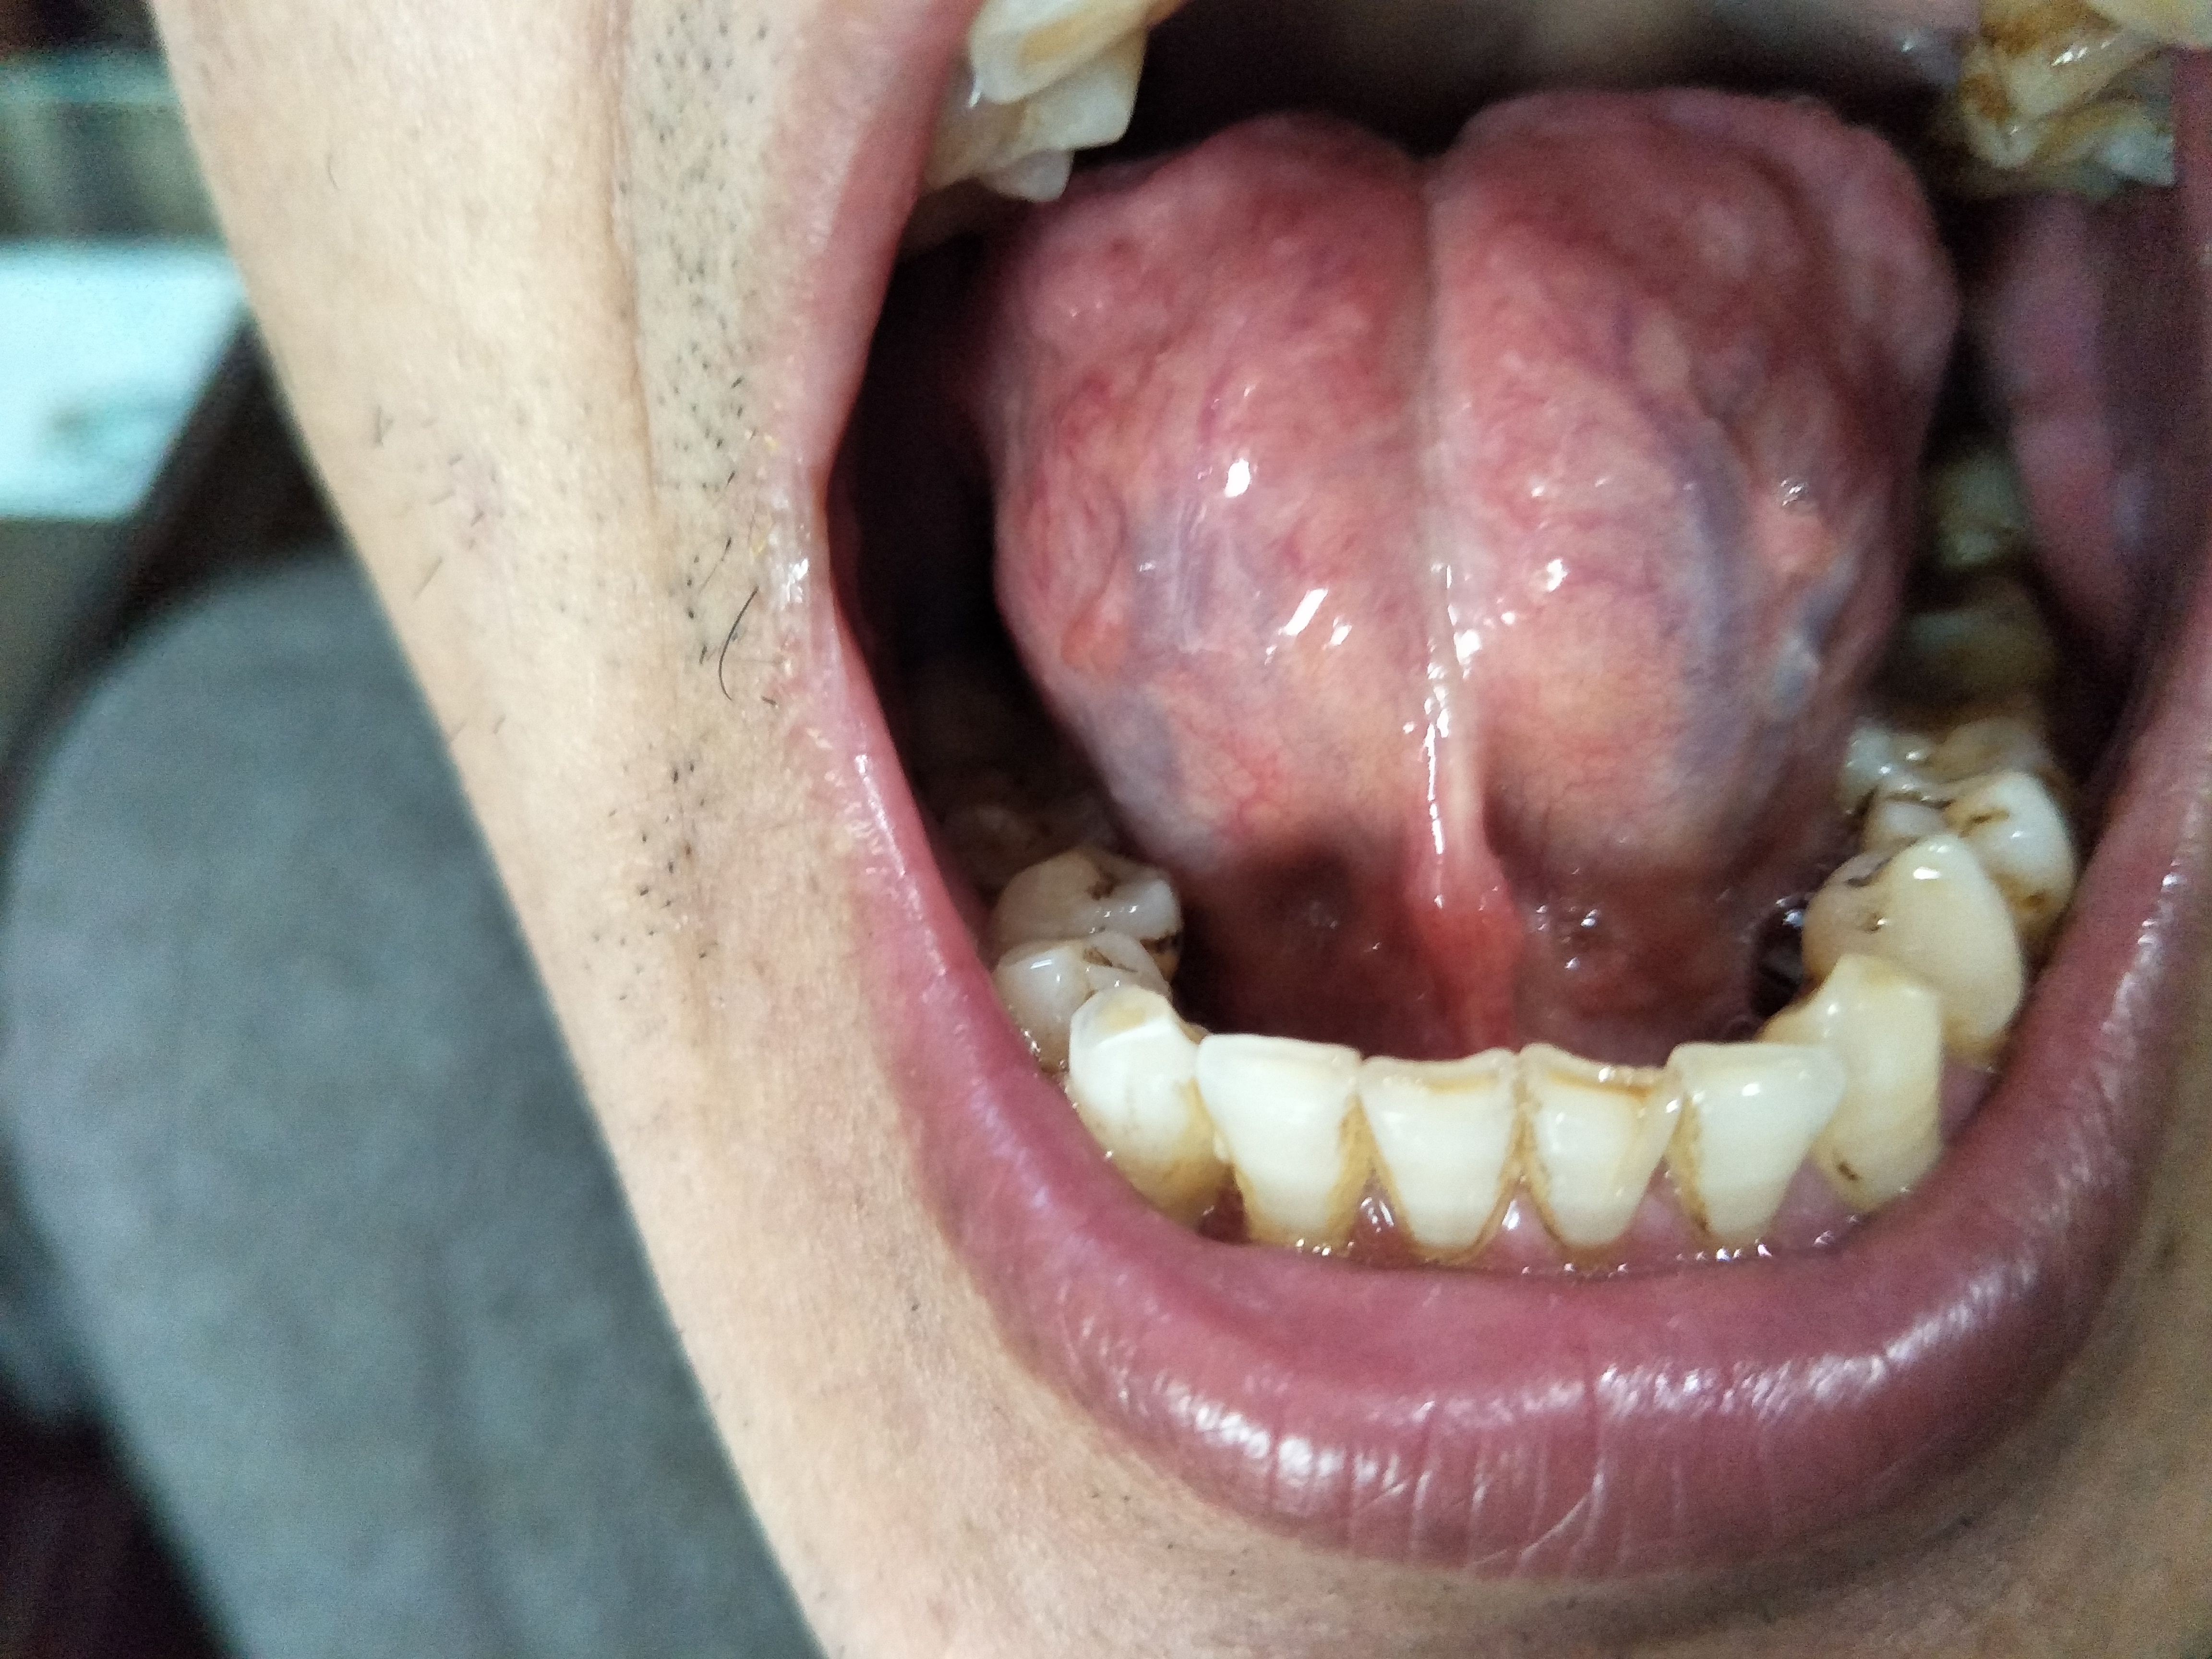

男,55岁。胃癌术后伴转移3年。(舌下)

发布时间:2021-06-24 发布人:储成志